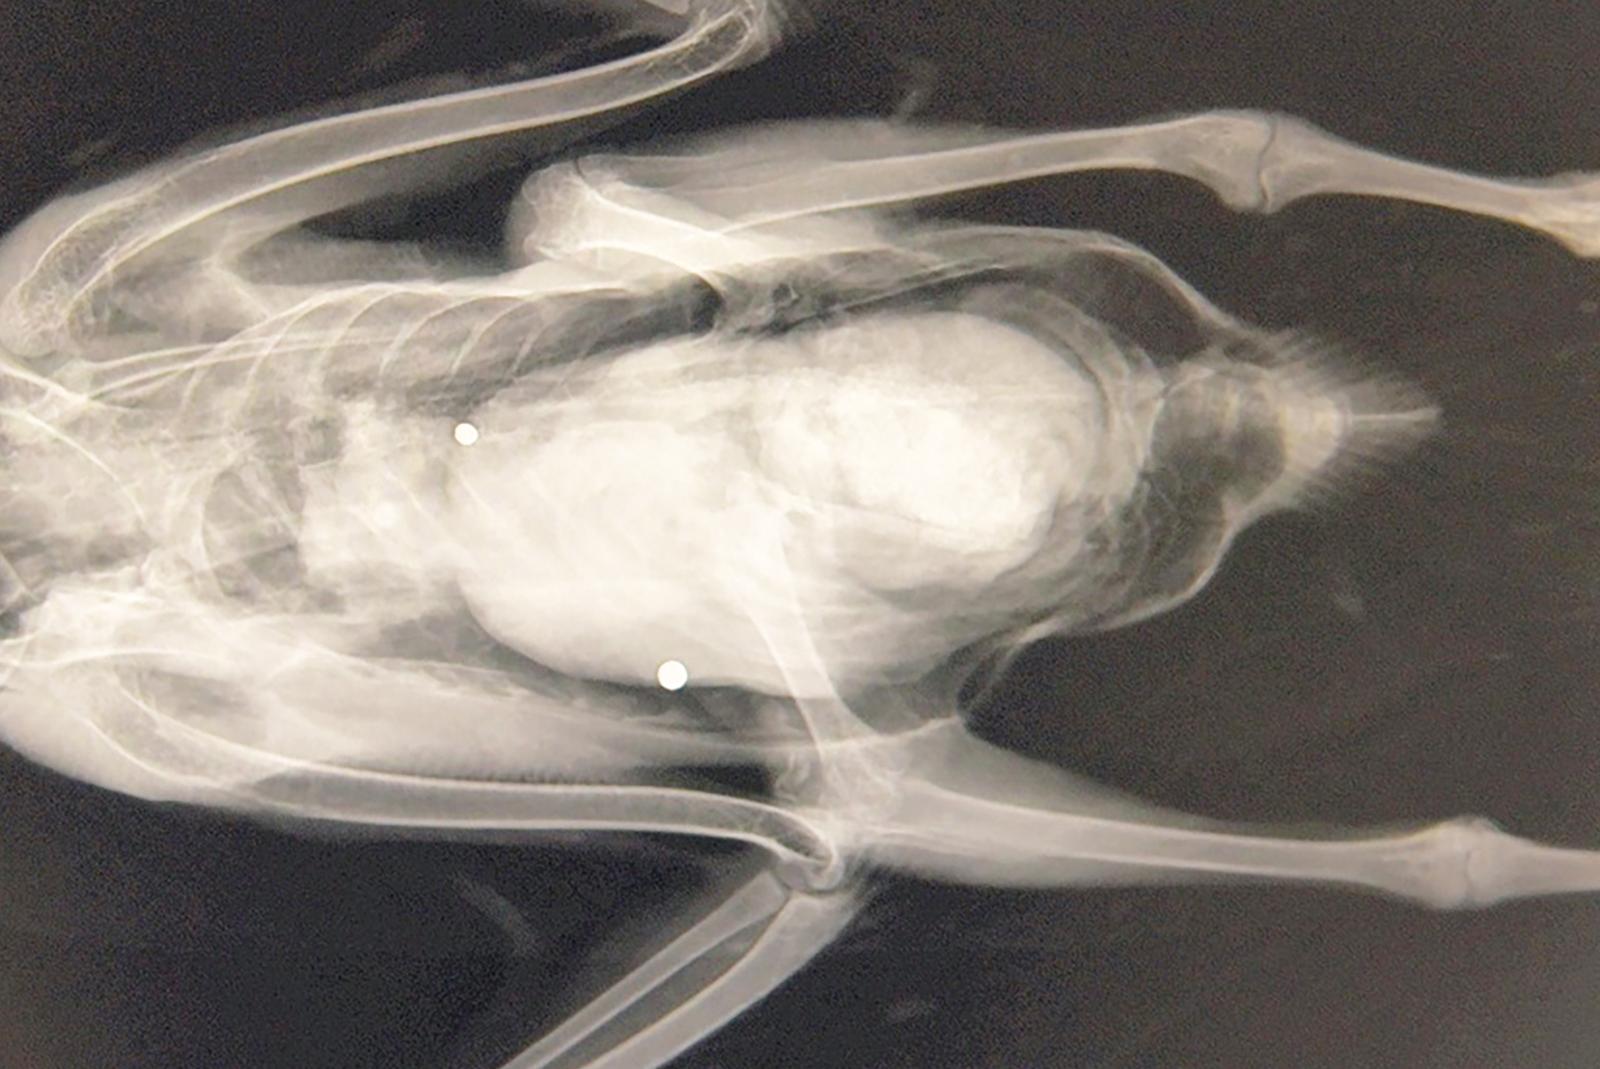

Erneut stehen Jäger im Verdacht, an der Ems geschützte Blässgänse abgeschossen zu haben. »Die Ermittlungen hierzu wurden aufgenommen und dauern an«, teilte Melina Trey, Pressesprecherin der Polizeiinspektion Leer/Emden, auf Anfrage mit. Vogelschützer haben Anzeigen ...